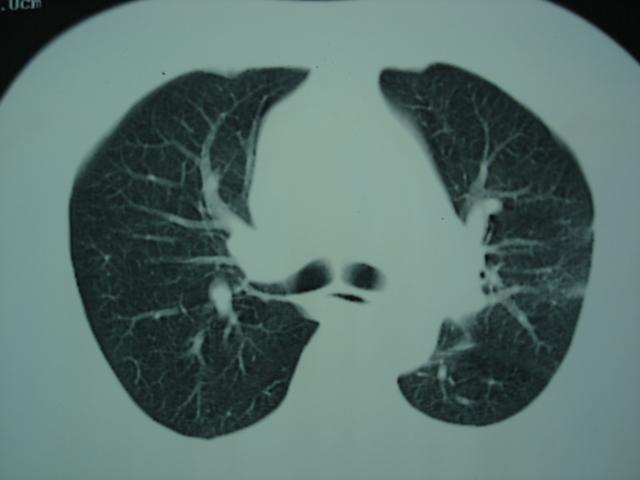

2009.6.4 2009.6.7 2009.8.21

第一次ct2009.6.4